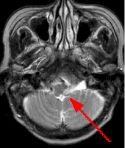

Fig. 1 Fig. 2 Fig. 3 Fig. 4

MRI Findings: In the supratentorial regions, some atrophy and chronic small vessel deep white matter ischemic changes were observed (Fig. 1) but no acute lesion or infarct was observed on MR diffusion. In the posterior fossa, however, a subtle small 1 cm hyperintensity can be seen in the left side of medulla on T2 weighted (Fig. 2) and FLAIR images (Fig. 3). This can be seen with an infarct, but its age would remain indeterminate. The MR diffusion image (Fig. 4) shows hyperintensity in the same region consistent with an acute infarct (arrows) as opposed to chronic ischemic changes.

Final Diagnosis: Based on the MR appearance, diagnosis of acute lateral medullary infarct was provided. This is a classic appearance of a posterior inferior cerebellar artery (PICA) infarct (PICA Syndrome), which may have thrombosed.